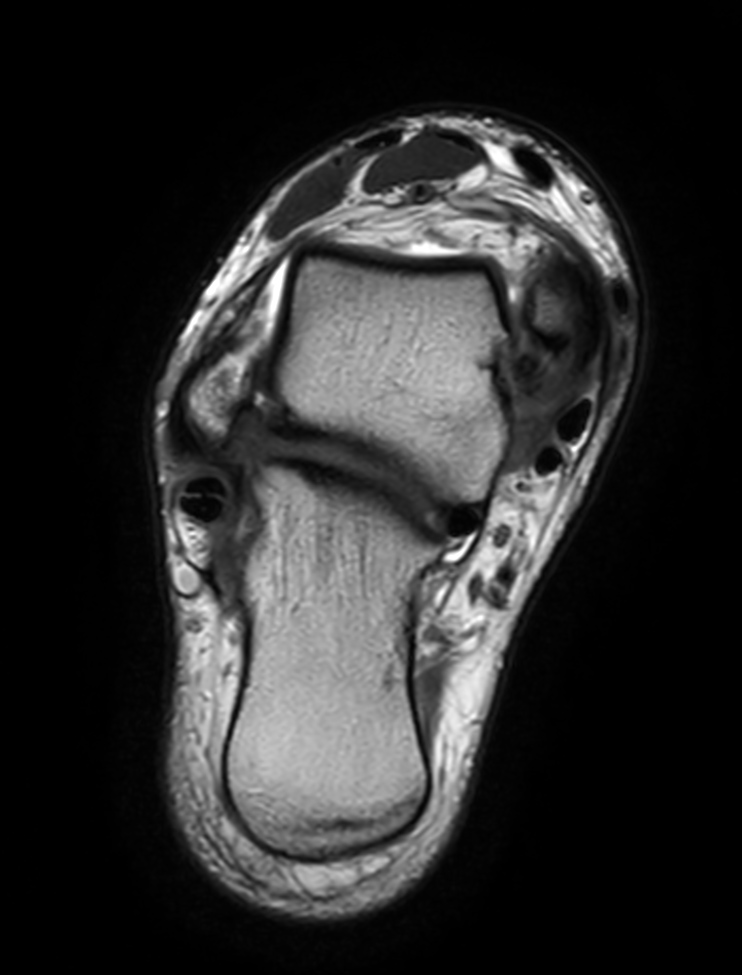

Axial T2w TSE